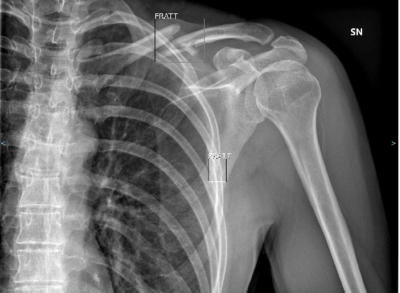

#Covid19: cosa rivelano Tac e radiografia sull’infezione